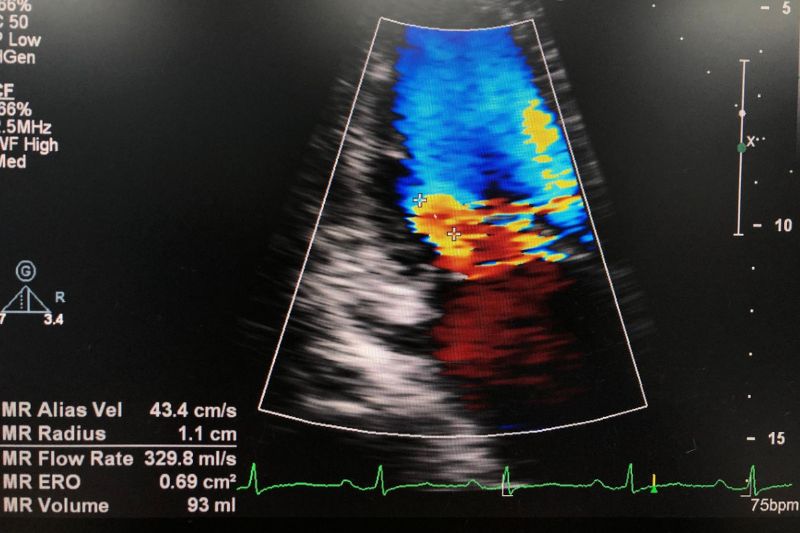

Dưới đây là một số hình ảnh hở van tim hai lá, giúp bạn hiểu rõ hơn về bệnh lý này:

Sử dụng sóng âm tạo ra hình ảnh tim đang đập, cho thấy cấu trúc van hai lá và lưu lượng máu trong tim. Bác sĩ thường chỉ định hai kỹ thuật chính là siêu âm tim qua thành ngực (TTE) hoặc siêu âm tim qua thực quản (TEE). (5)

Siêu âm tim qua thành ngực được thực hiện bằng cách đặt đầu dò lên thành ngực, tạo ra hình ảnh động của tim theo thời gian thực. Nhờ đó, bác sĩ chẩn đoán được mức độ, cơ chế hở van, đánh giá chức năng thất trái, áp lực động mạch phổi. Tuy nhiên, kỹ thuật này có thể không cung cấp đầy đủ dữ liệu. Lúc này, siêu âm tim qua thực quản nên được tiến hành, bằng cách đưa một ống mỏng qua miệng, xuống cổ họng, vào thực quản người bệnh. Hình ảnh van 2 lá sẽ hiện ra chi tiết, giúp quyết định phác đồ điều trị phù hợp.

Ngoài ra, tùy trường hợp, bác sĩ có thể áp dụng siêu âm Doppler để kiểm tra dòng chảy hở van, tăng áp phổi; hoặc siêu âm 2D, 3D nhằm xác định nguyên nhân, mức độ nghiêm trọng của hở van 2 lá, tình trạng vôi hóa vòng van.